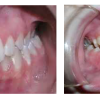

Kontaktist tekitatud kahjustused suulimaskestal

-Kontaktist põhjustatud mehhaanilist limaskesta kahjustust võivad esile kutsuda ortodontilised plaadid, breketid Harva põhjustavad kahjustusi täidismaterjalid. - Metalliärritust võivad anda breketid, aparaatide klambrid, hambakroonid – kroom, nikkel, berüllium, palladium, kloriid. Siia...